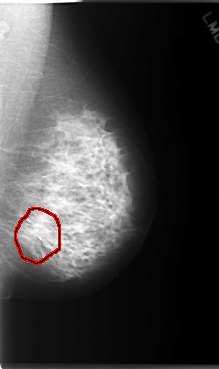

C_0070_1.LEFT_CC

LEFT_CC LINES 5960 PIXELS_PER_LINE 3576 BITS_PER_PIXEL 12 RESOLUTION 50 OVERLAY

FILE: C_0070_1.LEFT_CC.OVERLAY

TOTAL_ABNORMALITIES 1

ABNORMALITY 1

LESION_TYPE MASS SHAPE IRREGULAR MARGINS ILL_DEFINED

ASSESSMENT 4

SUBTLETY 3

PATHOLOGY MALIGNANT

TOTAL_OUTLINES 1

BOUNDARY